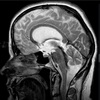

2.5cm lateral to the mouth